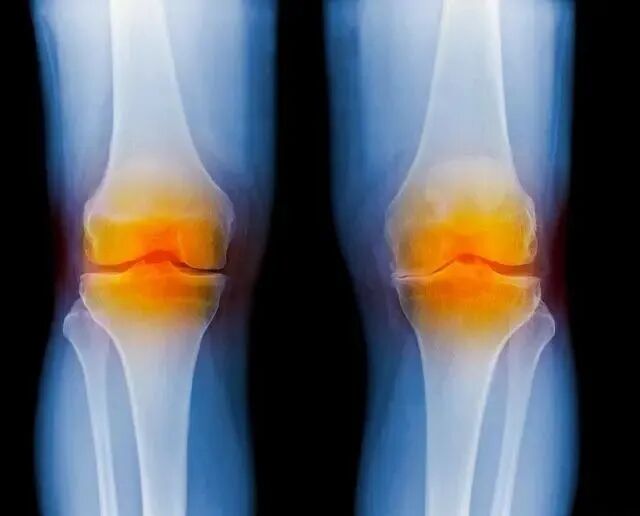

关节由骨、软骨、滑膜、关节囊、肌肉、韧带等组织构成,这些软组织保证关节稳定性。

关节腔是骨与骨间隙形成的密闭腔隙,其中充满关节软骨,滑膜如房间壁纸,正常分泌少量润滑液,润滑和保护关节软骨。

滑膜炎是滑膜受刺激产生炎症,导致分泌液失调形成积液的关节病变,膝关节滑膜多,滑膜炎较为多见。

关节受内外因素影响,滑膜反应,出现充血、水肿、渗液,表现为关节肿胀、疼痛、积液、活动受限。